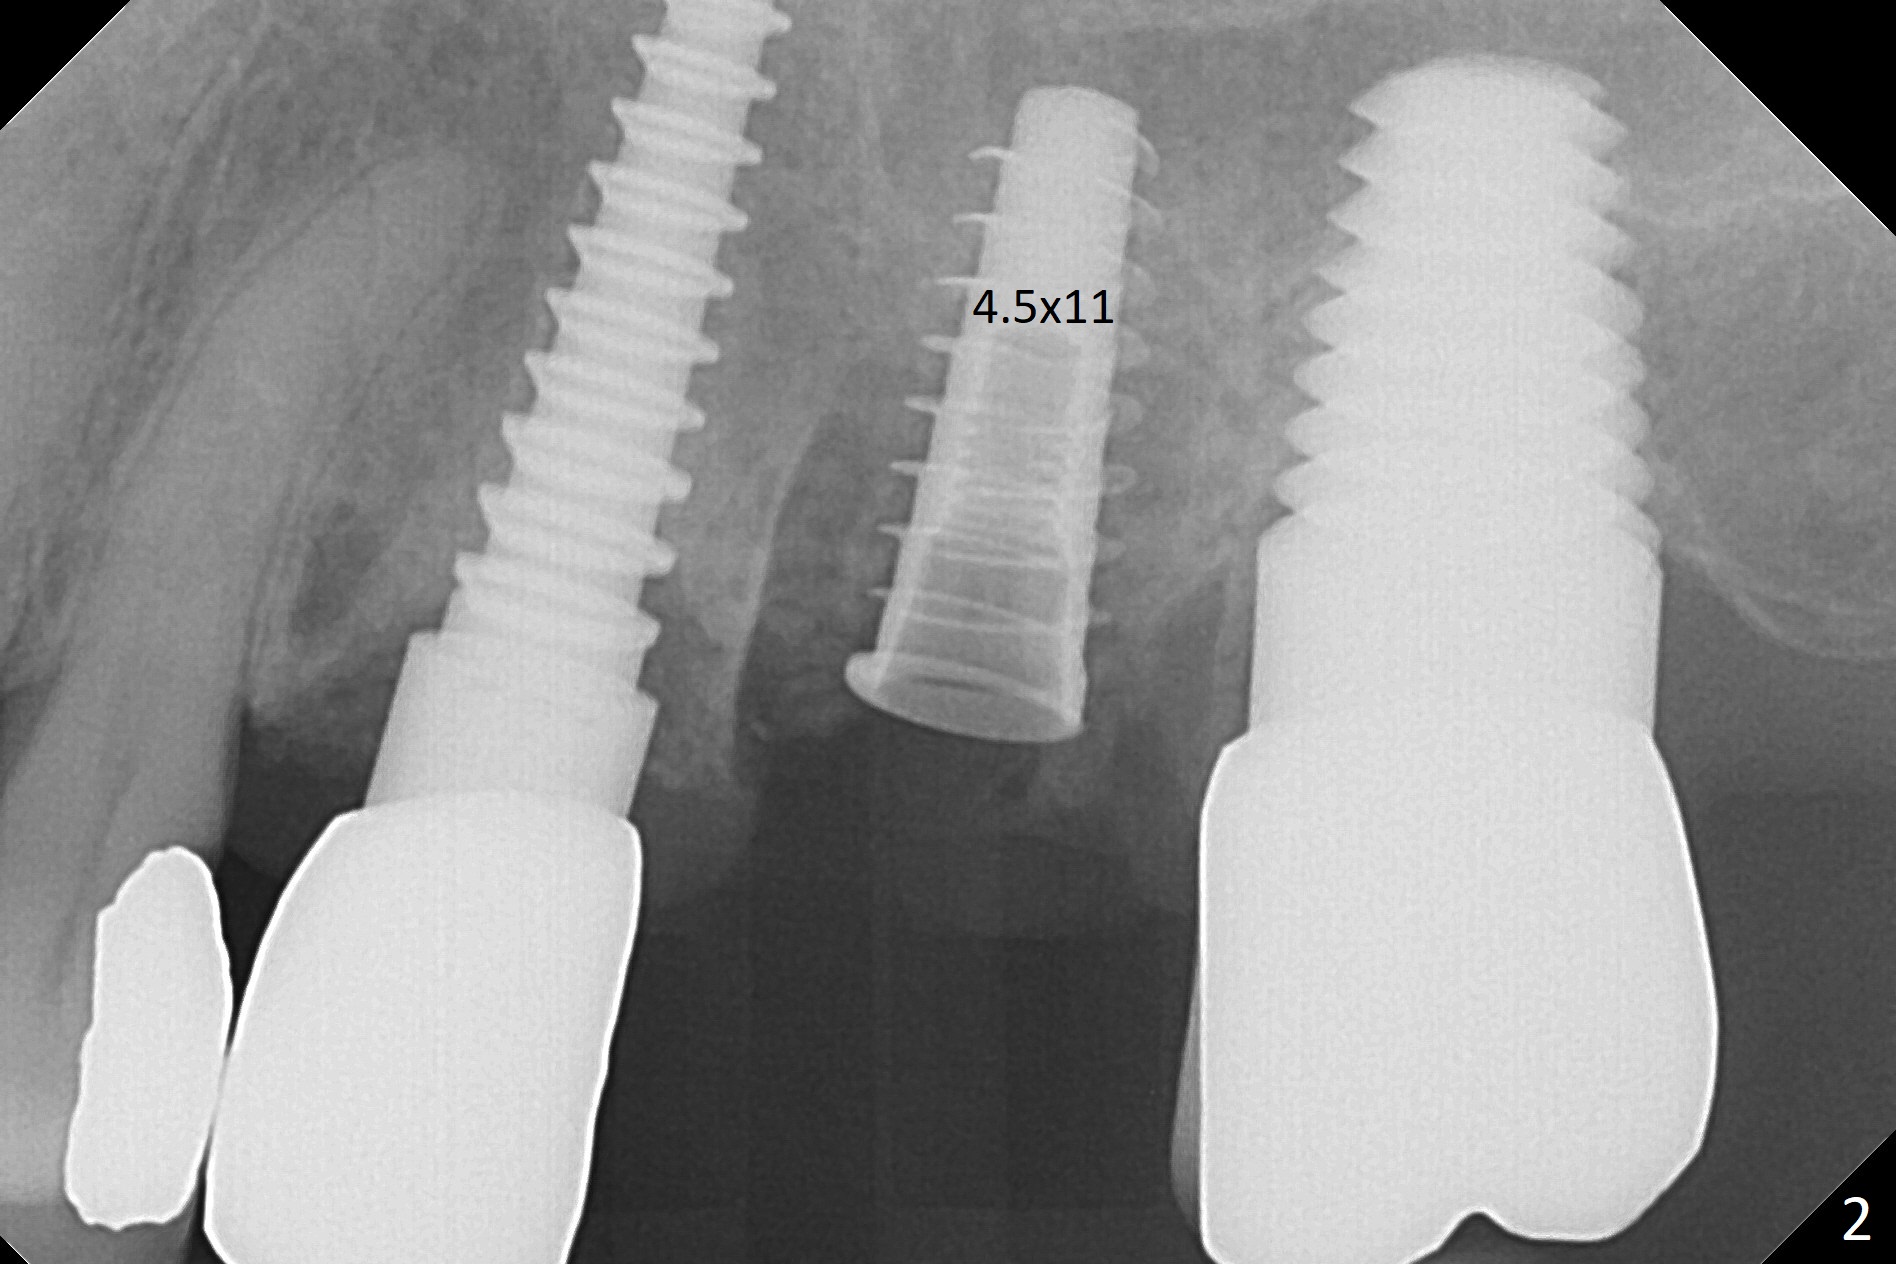

Initial osteotomy in the septum of the tooth #14 is 9 mm, approximately 2 mm from the sinus floor (Fig.1).  Subsequent osteotomy depth is 11 mm, followed by insertion of a 4.5x11 mm dummy implant (Fig.2).  After use of Magic Drill (MD) 4.8 mm for 9 mm, a 5x11 mm IBS implant is placed with sinus lift without additional bone graft (Fig.3 *).  In contrast, autogenous bone (from MD) and Vanilla Graft are meticulously placed in the remaining socket (+) before and after placement of a 6.5x5.7(2) mm abutment.  An immediate provisional is fabricated to close the sockets.  There is buccal tenderness 1-3 months postop.  There is distopalatal implant thread exposure.  A healing abutment (5.5x2 mm) is placed.  CT confirms thin buccal plate (Fig.4,5).  It appears that the implant should have been as palatal as possible.  The tenderness remains for the next 2 weeks.  When the healing abutment is removed, the implant seems to have been placed shallow, ~ 1 mm subgingival (Fig.6).  With local anesthesia, the implant is reversed to clean the coronal threads with Titanium brush and copious irrigation (Fig.7).  The implant is then placed ~4 mm subgingival (Fig.8) and slightly subcrestal (Fig.9,10).  It appears that the postop bone loss (Fig.9 *, as compared Fig.1,2) makes the implant look to be placed too shallow.  When the implant is being placed deeper, the buccal plate feels intact.  The early periimplantitis is apparently due to postop bone loss more than buccal placement, although certain degree of buccal bone resorption must occur.  A 6x4 mm healing abutment is placed.  Left facial swelling develops 2 days post implant elevation (Fig.11,12, as compared to preop (Fig.13)).  The left maxillary sinus cloud (Fig.12) appears to be a false positive finding, since the same feature exists prior to implant elevation (Fig.13).  Both sinuses look clear prior to implant elevation (Fig.14).  Amoxicillin switches to Augmentin and Flagyl, since the patient is reluctant to have the implant removed.  Finally the sinus infection is under control.  The patient feels left facial swelling 9 months postop (5 months post elevation) and reports left nasal discharge ~ 1 month earlier.  There is mild buccal plate tenderness.  The implant seems to be buccally placed (Fig.15,16), although there is no significant change radiographically (Fig.17).  The implant is removed with bone graft (Fig.18 *).  To avoid complication and failure, an immediate implant at the upper 1st molar should be short and placed deep.